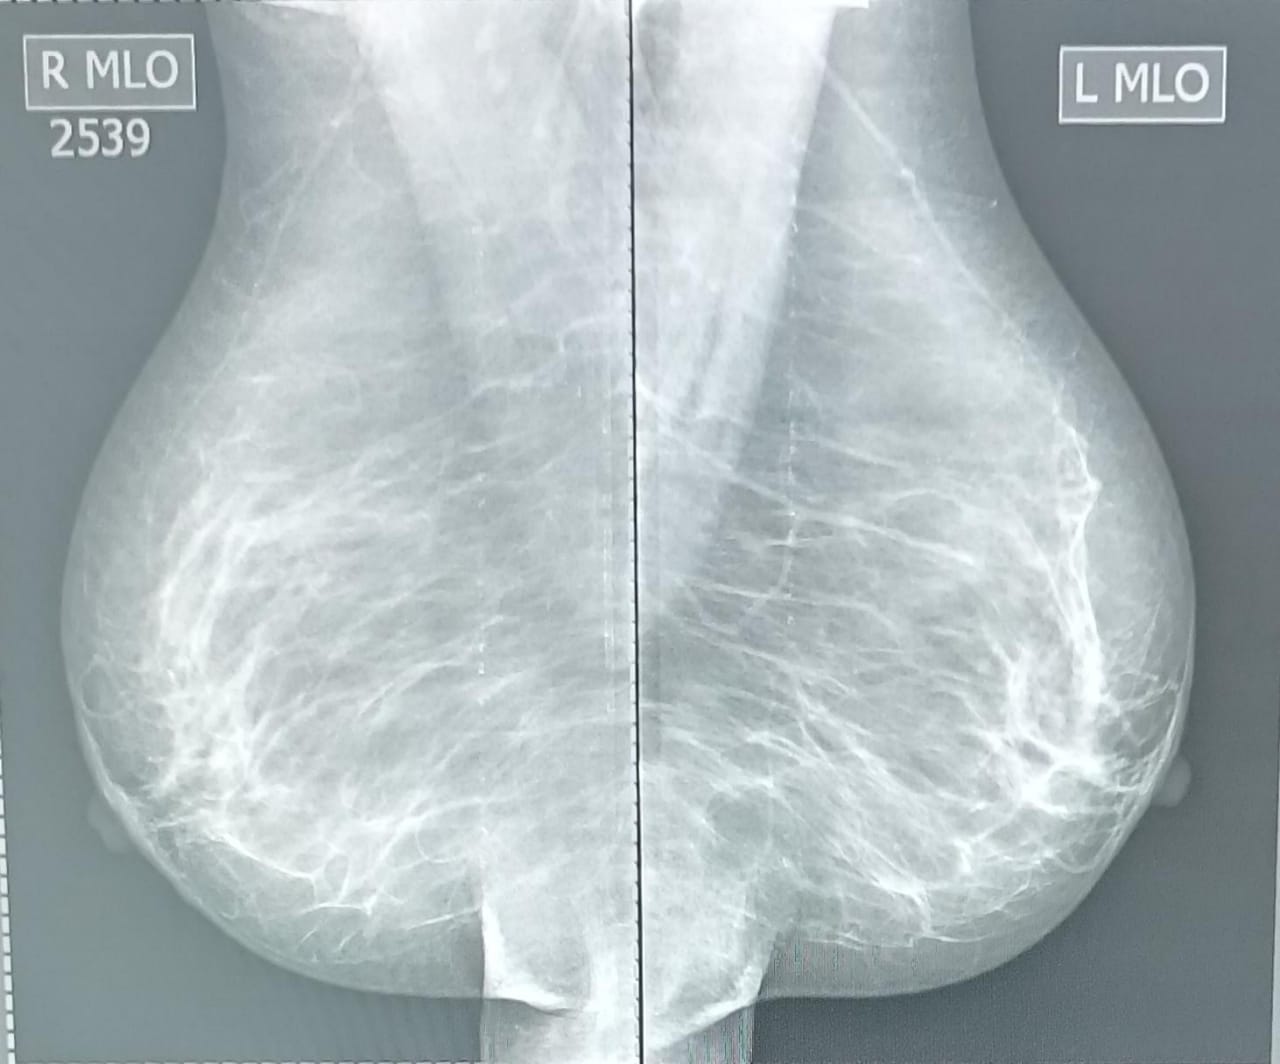

Маммография - рентгеновский метод исследования молочных желез. На сегодняшний день считается одним из самых информативных при диагностике доброкачественных и злокачественных новообразований. Выявленные новообразования могут быть доброкачественными и злокачественными опухолями, кистями. Таким образом, маммография - метод диагностики и профилактики рака. Это безболезненная и не вызывающая какого-либо дискомфорта процедура, длительность которой не превышает нескольких минут. Опасное заболевание, как рак грудной железы, может развиться не только у женщины, но также и представителя сильного пола. Если у мужчины любого возраста неестественно увеличилась одна или обе молочные железы, они стали болезненными, в них появились уплотнения или произошли какие-то другие изменения, необходима провести рентгенологическое исследование. Маммография - ее многие женщины избегают, якобы, из-за облучения. Да, обследование даёт лучевую нагрузку на организм. Но современные цифровые маммографы выдают такую низкую дозу облучения, что негативно на ваши молочные железы, да и организм в целом, это никак не повлияет. С профилактической целью маммографию молочных желез рекомендуется выполнять ежегодно всем женщинам старше 40 лет. Это связано с изменением гормонального фона, что повышает риск развития онкологических заболеваний.